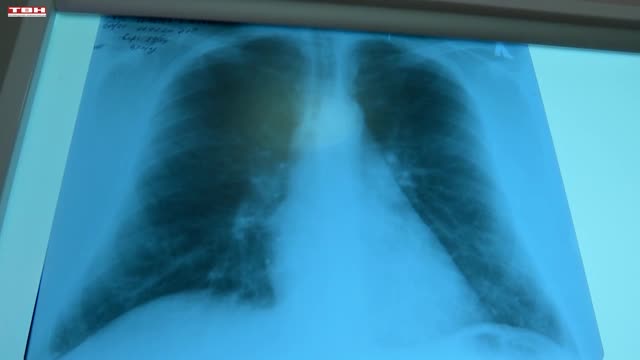

При обструктивной болезни легких изменяется проходимость бронхов. Дыхательные пути сужаются, организм недополучает кислород. В результате начинают сбоить все системы органов. Не допустить разрушительных последствий поможет профилактика.

Павел КОЛЬЦОВ, заведующий пульмонологическим отделением НГКБ № 29 им. А.А. Луцика: «Если уже курим, значит надо бросать курить. Это все-таки профилактические осмотры, рентгены не реже одного раза в год, плюс к этому исследование функции внешнего дыхания хотя бы раз в год, и если человек чаще чем 2 раза в год болеет ОРВИ, длительный кашель более 2 недель – это повод обращаться к доктору и проводить дальнейшее дообследование».